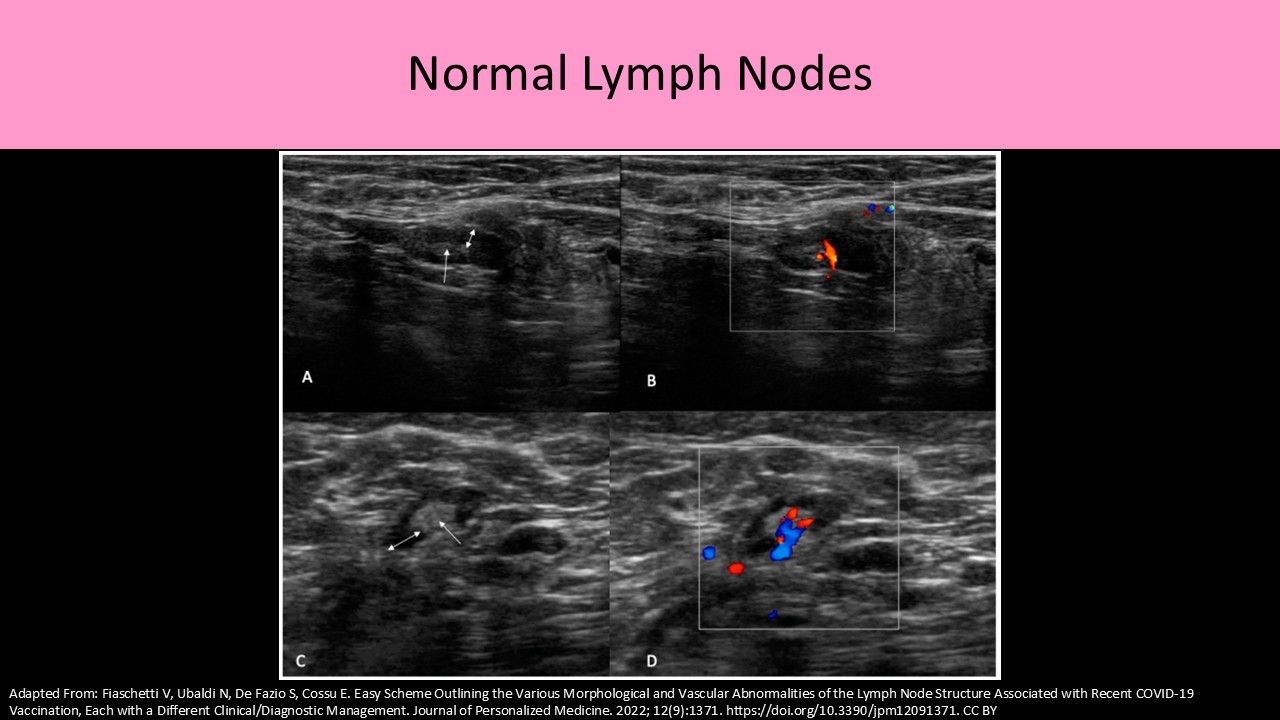

- Intramammary nodes are found within the breast parenchyma

- They are normally oval or reniform (kidney-shaped) in shape

- Lymph nodes are most concentrated in the upper outer quadrants